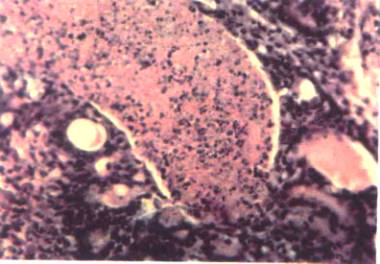

FOTOGRAFIA 7 Carcinoma ductal, Se puede observar la abundante proliferación celular alrededor de los ductos, importante pleomorfismo, mitosis e hipercromasia. 320 X

FOTOGRAFIA

8 Carcinoma ductal, variedad comedocarcinoma.

La imagen muestra la característica necrosis intratumoral. 310 X